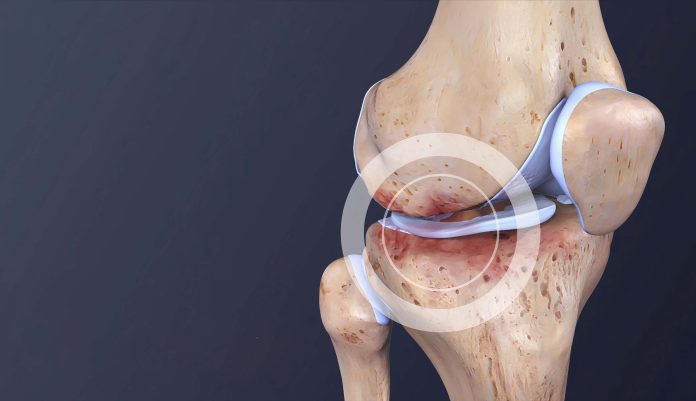

Hrskavica je elastično tkivo koje se nalazi između kostiju u zglobovima. Njena osnovna funkcija je smanjenje trenja prilikom pokreta, što omogućava glatke i nesmetane pokrete. Bez adekvatne hrskavice, kosti bi se sudarale i to bi uzrokovalo bol, oštećenja, pa čak i trajne disfunkcije zglobova. Osim toga, hrskavica se teško obnavlja jer ne sadrži krvne žile, što je čini podložnom oštećenjima uzrokovanim starenjem, povredama ili prekomjernim naporima tokom fizičkih aktivnosti. S obzirom na sve navedeno, od esencijalne je važnosti da se posvetimo očuvanju zdravlja hrskavice i zglobova.

Jedan od prvih simptoma oštećenja hrskavice su bolovi u zglobovima, ukočenost i smanjena pokretljivost. Ovi simptomi često su prvi znakovi da je vrijeme da obratite pažnju na svoje zdravlje. Ignoriranje ovih signala može dovesti do ozbiljnijih problema kao što je artritis, koji se može razviti kada se upalni procesi u zglobovima ostave bez nadzora. Ključ za prevenciju leži u pravovremenom prepoznavanju simptoma i reagiranju na njih. U slučaju da primijetite ove simptome, odmah se konzultirajte sa stručnjakom.